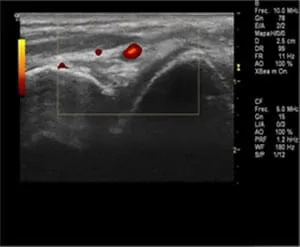

Es de vital importancia que tras una exploración completa desde el primer momento, nos den con un diagnóstico acertado. Con el fin, de que nos receten el tratamiento más adecuado en cada caso para nosotros. Con una exploración manual y un estudio ecográfico se puede concluir un diagnóstico óptimo.

Reconocerlo mediante la palpación manual y observando si se hincha más o menos no es suficiente para su correcto diagnóstico. Se necesitan una adecuada historia clínica y una exploración detallada.